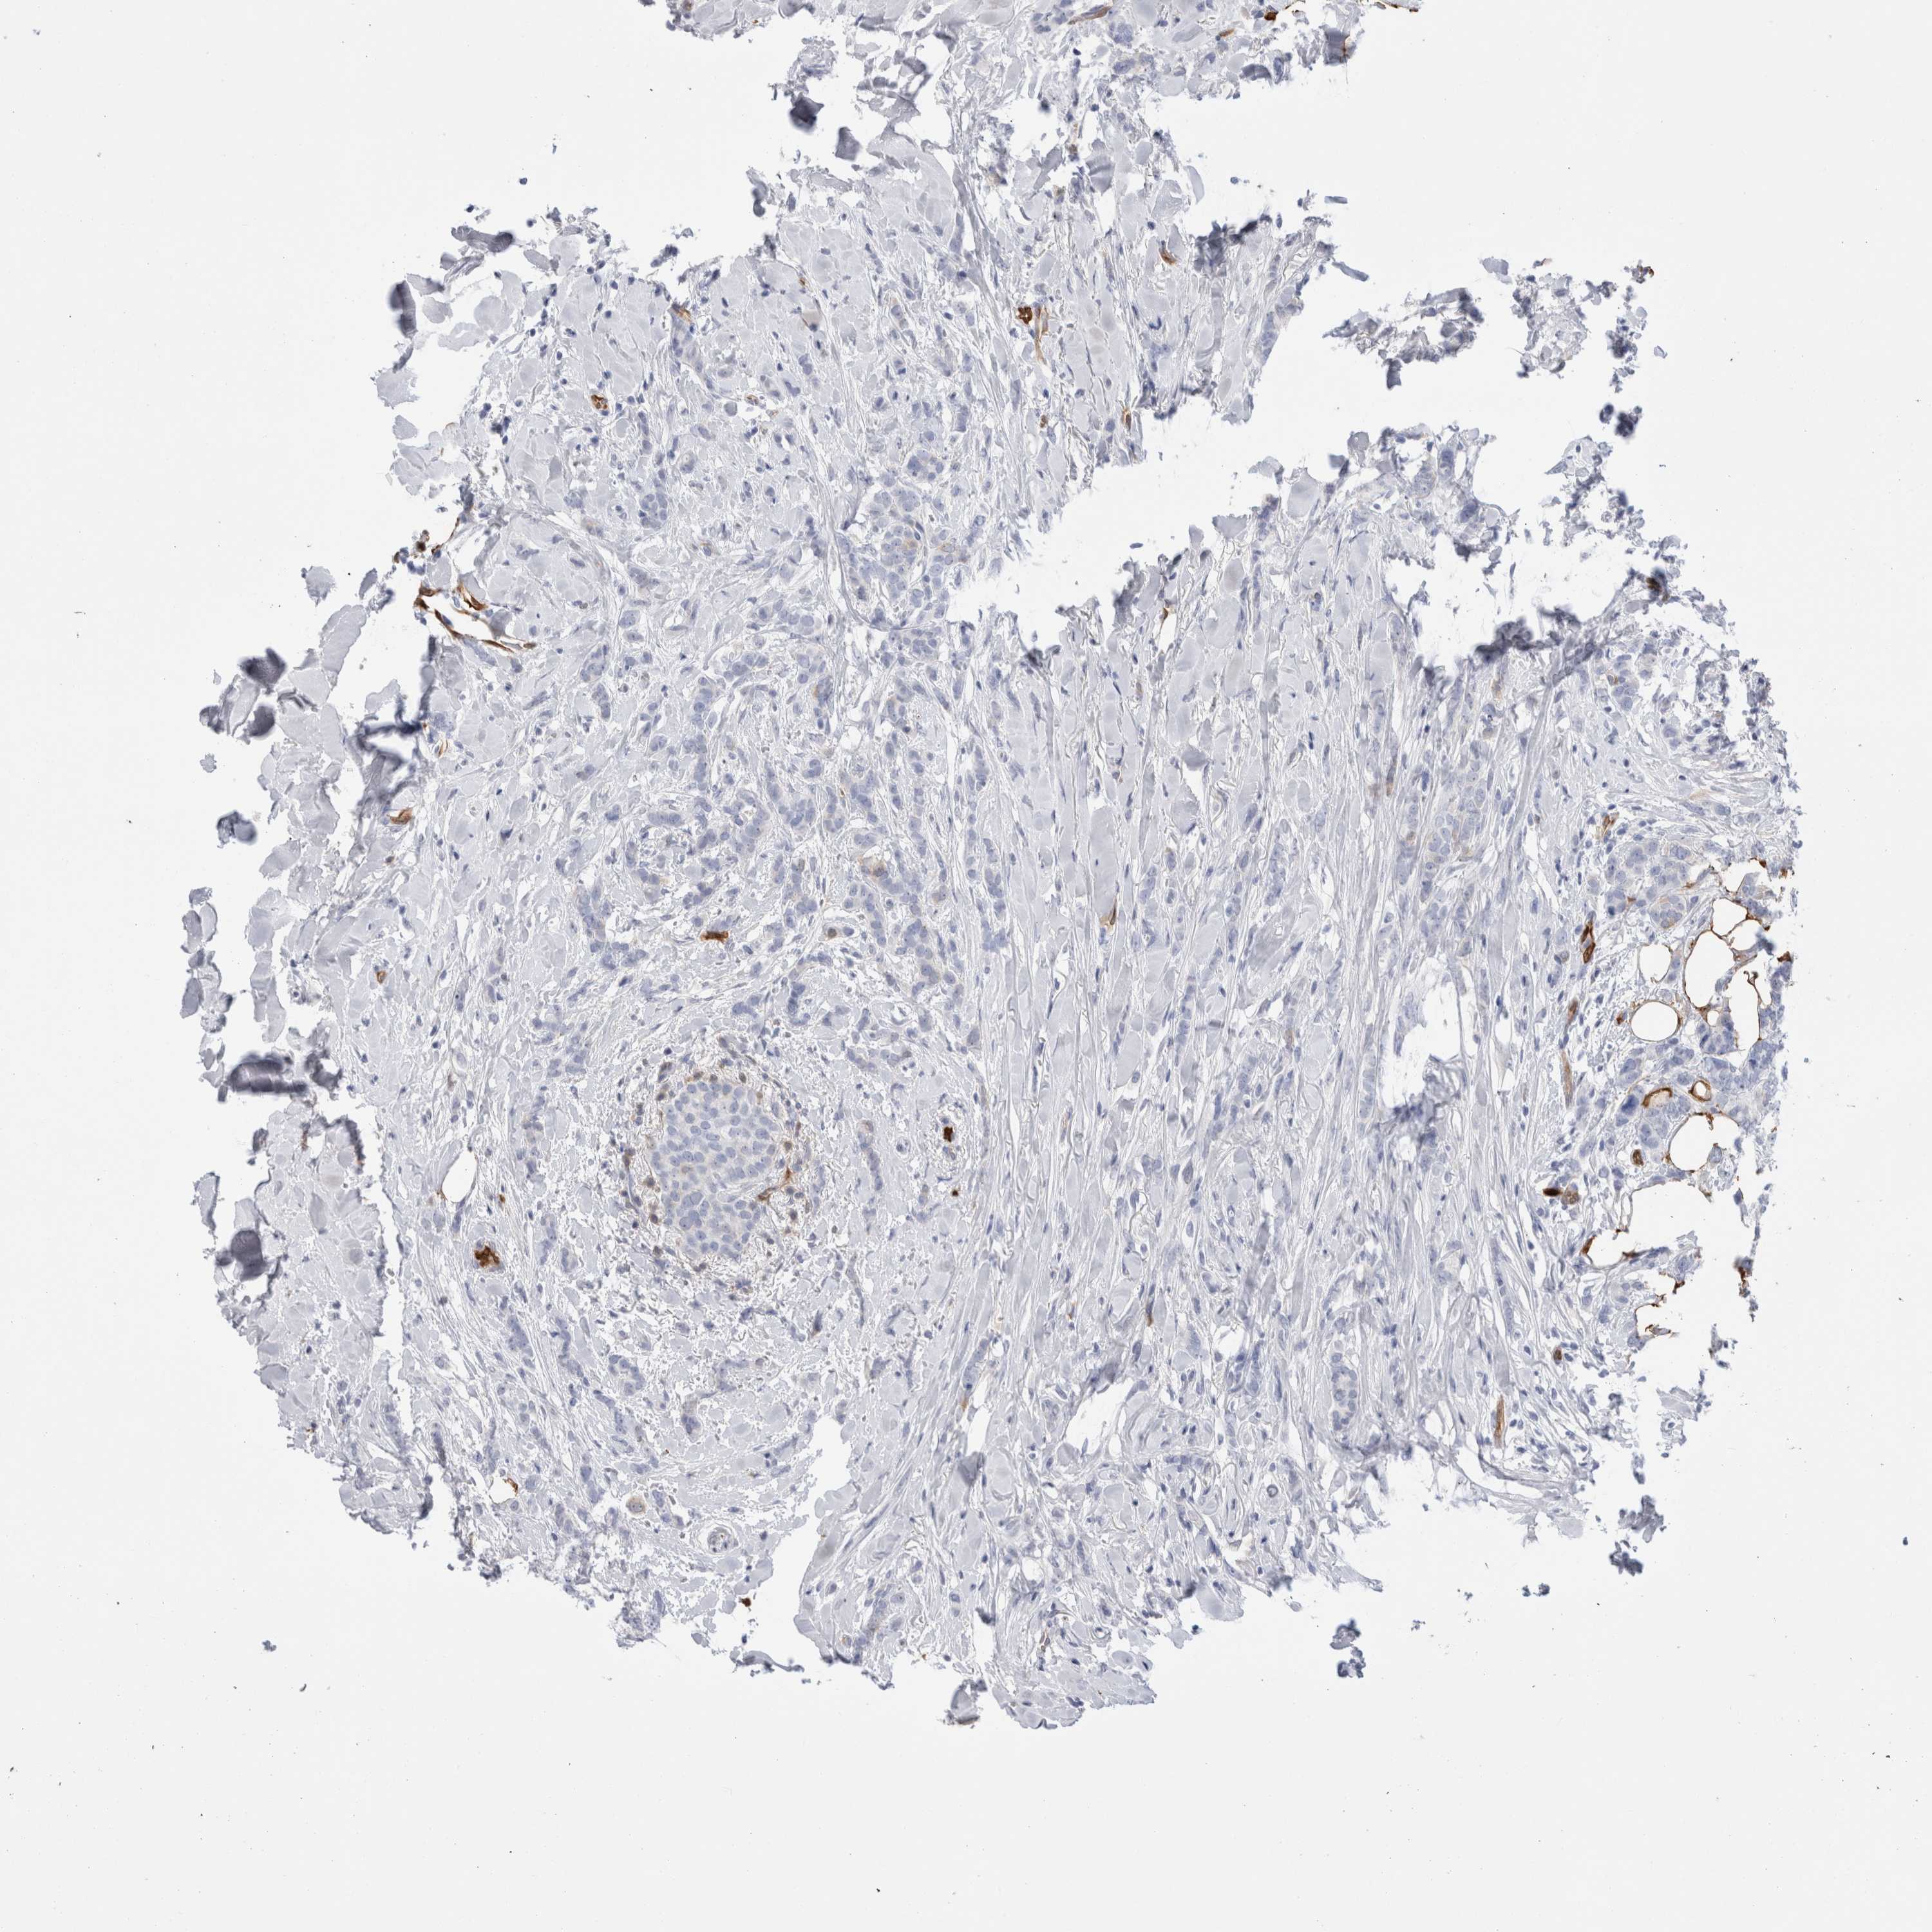

CANCER BREAST CANCER Show tissue menu

BRCA TCGA BRCA VALIDATION PROTEIN EXPRESSION

ANTIBODIES

AND

VALIDATION